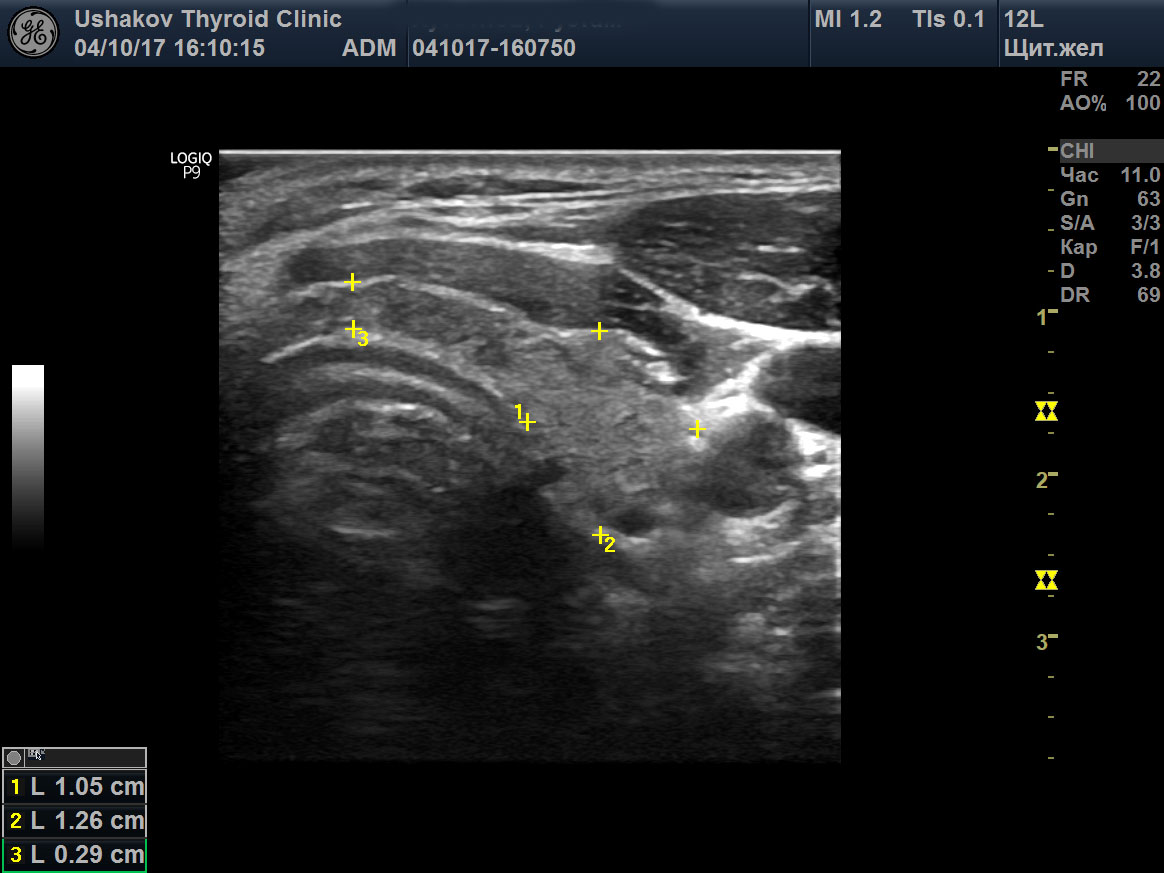

Гипертиреоз узи

Гипертиреоз узи 110 фото